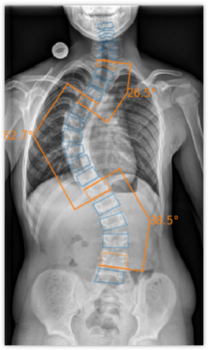

Die zugrunde liegende Technologie der Software von ImageBiopsy Lab basiert auf maschinellem Lernen – also darauf, dass Computer aus Beispielen vorheriger Fälle lernen. Tausende Röntgenbilder, von Ärzt*innen manuell markiert, dienen als Trainingsdaten: Sie zeigen der Software, wo etwa Gelenkspalten, Knochenwinkel oder Brüche liegen. Das System lernt, ähnliche Strukturen in neuen Bildern automatisch zu erkennen und zu vermessen. Die Lösungen von ImageBiopsy Lab erkennen in Sekundenschnelle relevante Strukturen, messen definierte Parameter und erzeugen einen strukturierten Analysebericht – standardisiert und reproduzierbar. So entsteht eine belastbare Grundlage für Diagnostik, Verlaufskontrolle und Therapieentscheidungen.

Heute hat ImageBiopsy Lab sieben zertifizierte Module ((MDR/TÜV SÜD, teil auch von der US-FDA) auf dem Markt. Sie decken zentrale anatomische Regionen wie Knie, Hüfte, Wirbelsäule oder Fuß ab und liefern standardisierte Analyseberichte, die in radiologischen und orthopädischen Praxen in Deutschland, Österreich und der Schweiz eingesetzt werden. Installiert „on-premise“ laufen sie im Hintergrund und liefern Zusatzinformationen direkt zum Bild.

Bekannt sind die Produkte auch für ihre ungewöhnlichen Namen: KOALA, LAMA, HIPPO, SQUIRREL, FROG und FLAMINGO. Was spielerisch klingt, folgt einer klaren Logik.

„Unser erstes Produkt hieß KOALA – das stand für Knee Osteoarthritis Labeling Assistant“, erklärt Ljuhar. Der Name kam im Team so gut an, dass Image Biopsy Lab das Schema fortgeführt hat. Heute sind alle Module Teil des „IB Lab Zoo“ – eines digitalen Ökosystems für muskuloskelettale Diagnostik.